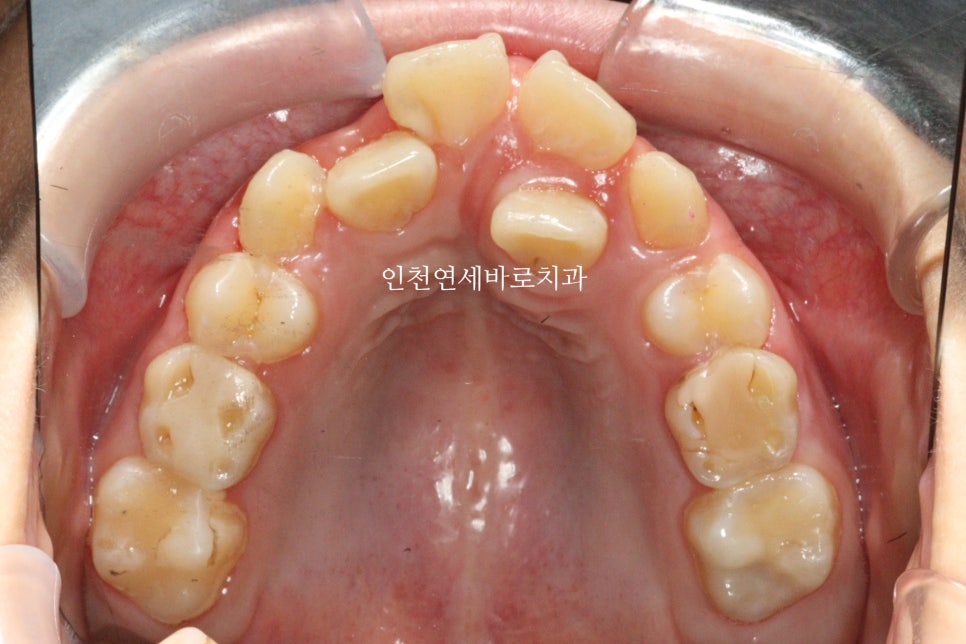

심한 덧니를 가진 아이가 병원에 왔습니다.

비발치 치료계획을 세운뒤 #인비절라인퍼스트 주문을 했습니다.

약한달이 지나고 치료를 처음 시작한 날의 모습입니다.